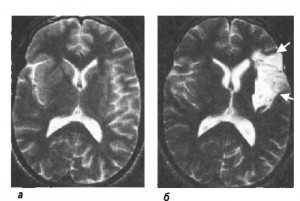

Выделяют острую и хроническую ишемию головного мозга. Острая ишемия возникает при резком развитии кислородного голодания и протекает по типу транзиторной ишемической атаки или ишемического инсульта (инфаркта мозга). Хроническая ишемия формируется постепенно в ответ на длительно существующую недостаточность мозгового кровообращения.

При 3-й стадии ХИМ более выраженными оказываются объективные неврологические расстройства в виде дискоординаторного, пирамидного, псевдобульбарного, амиостатического, психоорганического синдромов. Чаще наблюдаются пароксизмальные состояния — падения, обмороки. В стадии декомпенсации возможны нарушения мозгового кровообращения в виде «малых инсультов», или пролонгированного обратимого ишемического неврологического дефицита, длительность очаговых расстройств при котором составляет от 24 ч до 2 нед. При этом клиника диффузной недостаточности кровоснабжения мозга соответствует таковой при энцефалопатии средней степени выраженности. Другим проявлением декомпенсации могут быть прогрессирующий «законченный инсульт» и остаточные явления после него. Этой стадии процесса при диффузном поражении соответствует клиническая картина выраженной энцефалопатии. Очаговая симптоматика нередко сочетается с диффузными проявлениями мозговой недостаточности. Лечение на данной стадии имеет скорее поддерживающий характер, так как большая часть повреждений головного мозга и утраченных вследствие этого функций необратима.